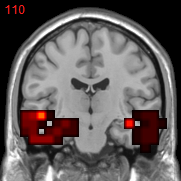

Usually, the first step of voxel-based neuroimage analysis requires preprocessing the T1-weighted image, such as segmentation and registration of grey matter (GM), white matter (WM) and cerebral spinal fluid (CSF). However, some systematic biases due to scanner difference and different population etc., can be introduced in this pipeline [2]. Part of them can be helpful to the discrimination of subjects from normal controls (NC), but may not be directly related to the disease. For example in structural Magnetic Resonance Imaging (sMRI) images of subjects with Alzheimer’s Disease (AD), after spatial normalization during simultaneous registration of GM, WM and CSF, the GM voxels surrounding lateral ventricle and subarachnoid space etc. may be mistakenly enlarged caused by the enlargement of CSF space in those locations [2] compared to normal template, as shown in Fig. 1. Although these voxels/features are highly correlated with disease, they can’t be regarded as lesion features in an interpretable model. In this paper we refer to them as “Procedural Bias”, which should be identified but is neglected in the literature. We observe that it can be harnessed in our voxel-based image analysis to improve the prediction of disease.

Figure 1: The overlapped voxels among top 150 negative value voxels in each fold of βpresubscript𝛽𝑝𝑟𝑒\beta_{pre} at the time corresponding to the best average prediction result in the path of GSplit LBI using 10-fold cross-validation. For subjects with AD, they represent enlarged GM voxels surrounding lateral ventricle, subarachnoid space, edge of gyrus, etc.

The process of feature selection combined with prediction accuracy can be analyzed together along the path. The result of 30ADNC is used as an illustration in Fig. 3. We can see that βpresubscript𝛽𝑝𝑟𝑒\beta_{pre} (blue curve) outperforms βlessubscript𝛽𝑙𝑒𝑠\beta_{les} (red curve) in the whole path for additional procedural bias captured by βpresubscript𝛽𝑝𝑟𝑒\beta_{pre}. Specifically, at βpresubscript𝛽𝑝𝑟𝑒\beta_{pre}’s highest accuracy (t5subscript𝑡5t_{5}), there is a more than 8%percent88\% increase in prediction accuracy by βpresubscript𝛽𝑝𝑟𝑒\beta_{pre}. Early stopping regularization at t5subscript𝑡5t_{5} is desired, as βpresubscript𝛽𝑝𝑟𝑒\beta_{pre} converges to βlessubscript𝛽𝑙𝑒𝑠\beta_{les} in prediction accuracy with overfitting when t𝑡t grows. Recall that positive (negative) features represent degenerate (enlarged) voxels. In each fold of βpresubscript𝛽𝑝𝑟𝑒\beta_{pre} at t5subscript𝑡5t_{5}, the commonly selected voxels among top 150 negative (enlargement) voxels are identified as procedural bias shown in Fig. 1, where most of these GM voxels are enlarged and located near lateral ventricle or subarachnoid space etc., possibly due to enlargement of CSF space in those locations that are different from the lesion features.